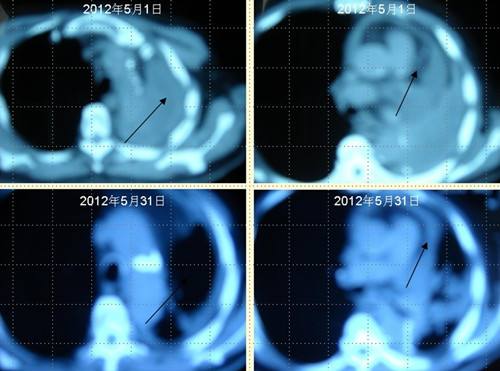

患者王某某,男,74歲,于2009年12月在濱州醫學院附屬醫院行左肺下葉占位切除術,術后病理提示為"中分化鱗狀細胞癌"侵犯支氣管壁全層,累及支氣管周圍肺組織。術后化療4個周期,局部放療30次(具體方案及劑量均不詳),2011年病灶局部復發,口服"特羅凱""康力欣"等無效,于2012年5月1日復查肺CT示:心包積液,左側包裹性胸腔積液,后縱膈結節影,右側少量積液。經采用"中醫調胃、強腎、止血、化巖法"治療1個月,胸腔積液完全消失,心包積液明顯減少,未出現新癌灶。

肺癌王XX采用 “董氏治癌法”治療前后CT對照變化